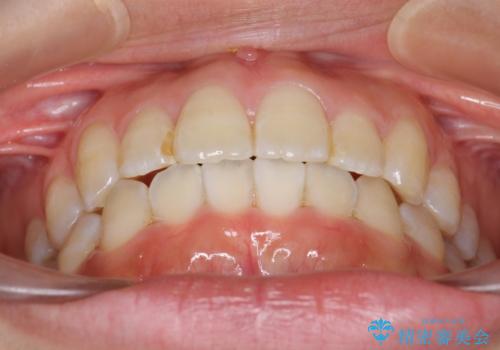

上下の前歯のがたつき 歯を抜かずに矯正

- 上下の前歯のがたつきを主訴に来院。

歯を抜かずに前歯を揃えています。

奥歯を後ろに下げたりなどはしていません。

奥歯を外に広げ、前歯中心に歯を少し削っていますが、健康には問題ない範囲で行なっています。